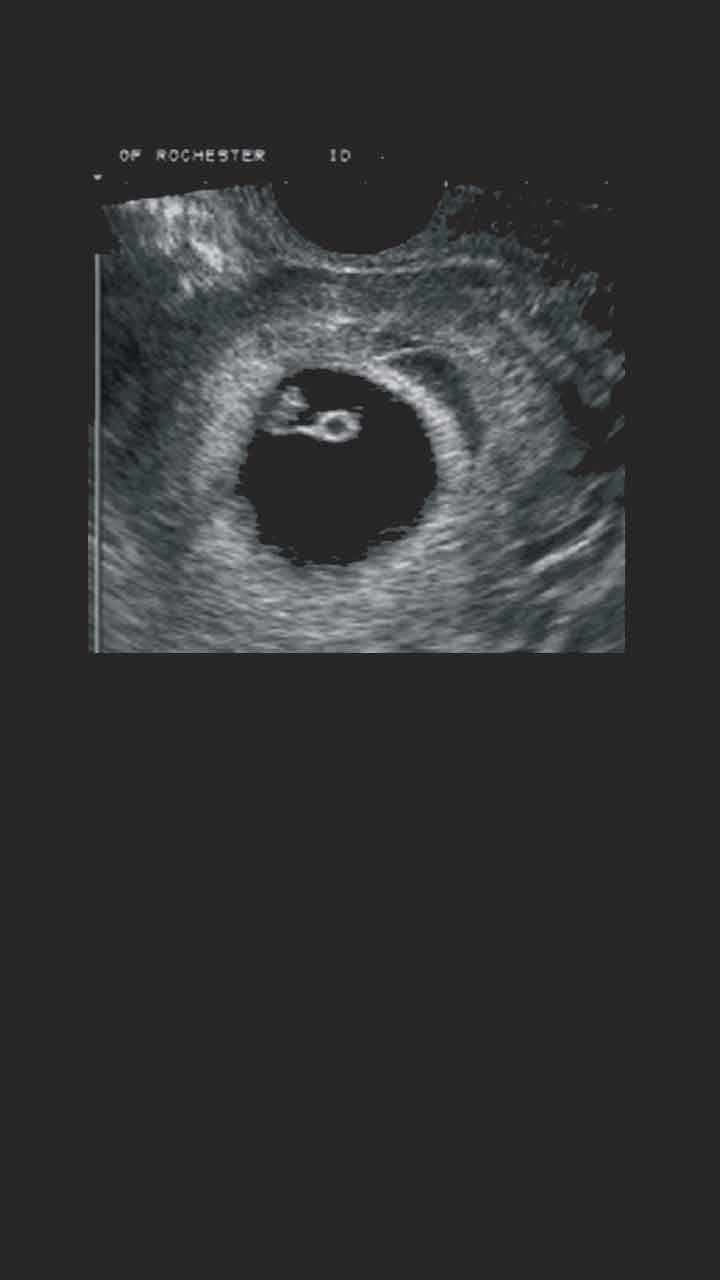

Haftasında annede meydana gelen değişimler hamileliğin ilk haftalarındaki belirtilere ek olarak 9. 34 haftalik bebek ultrason görüntüsü üç veya dört boyutlu ultrason gebeliğin ilk aylarından itibaren yapılabilmektedir. 9 haftalık bir gebelikte bebek, ultrasonda rahatlıkla görülebilecek boyuta ulaşmıştır. Dokuz haftalık gebelikte bebeğin boyu yaklaşık 2 cm, ağırlığı 2 gram kadardır. Dokuzuncu hafta bebek gelişimi ayrıntılı ultrason videosu. Haftada bebek hareketleri devam eder, bebek hareket ettikçe kasları güçlendir.

Anne karnındaki 9 haftalık bebeğin görüntüsü. Dokuz haftalık gebelikte bebeğin boyu yaklaşık 2 cm, ağırlığı 2 gram kadardır. 34 haftalik bebek ultrason görüntüsü üç veya dört boyutlu ultrason gebeliğin ilk aylarından itibaren yapılabilmektedir. 9 haftalık bir gebelikte bebek, ultrasonda rahatlıkla görülebilecek boyuta ulaşmıştır. Kalp kapakları, burun ucu ve retina tabakası da 9. Haftada bazı annelerde varis ve basur şikayetleri görülebilir.

9 haftalık bir gebelikte bebek, ultrasonda rahatlıkla görülebilecek boyuta ulaşmıştır. 9 haftalık bebek ultrasonda başı her zamanki gibi göğsüne ve karnına doğru durur. Ayakları vücudunun ortasına doğru yaklaşıyor.

9 haftalık bebeğin ultrason görüntüsü 9 haftalık bebek ultrason görüntüsü incelendiğinde ellerini kalbinin üzerinde birleştirdiği görülebilir. Son adet tarihine göre 9. 9 haftalık gebelik hamilelik görüntüsü 10 şub 2017.

9 haftalık bir gebelikte bebek, ultrasonda rahatlıkla görülebilecek boyuta ulaşmıştır. Bu hareketler 9 haftalık bebeğin ultrason görüntüsünde seçilebilir. Gözler gelişir, dil oluşmaya başlar.

Elleri, bilekten kıvrılarak kalbinin üst kısmında duruyor. Ama minik tekme ve yumruklarını senin hissedebilmene. 9 haftalık gebelik ultrason görüntüsünde bebeğinizin gözlerinin net bir şekilde göründüğünü fark edebilirsiniz.

9 haftalık gebelik ultrason görüntüleri; 9 haftalık bebek ultrasonda başı her zamanki gibi göğsüne ve karnına doğru durur. Bu haftalar bebeğinizin kollarının ve bacaklarının uzamaya devam ettiği haftalardır.

Bu hafta bebeklerin başı henüz eğik durur ve yuvarlaklaşmaya başlar. Bu hareketler 9 haftalık bebeğin ultrason görüntüsünde seçilebilir. Onuncu haftada bebek bütün organ sistemleri gelişmiş olduğu için artık embriyo değil fetus olarak adlandırılır ve bu hafta fetal dönemin başlangıcıdır.

Haftada bazı annelerde varis ve basur şikayetleri görülebilir. Bebeğinizin ayakları vücudunun ortasına doğru yaklaşmış ve c harfi görüntüsü ile neredeyse bir insan görünümüne ulaşmıştır. 9 haftalık gebelik ultrason görüntüsünde bebeğinizin gözlerinin net bir şekilde göründüğünü fark edebilirsiniz.

9 haftalık bebeğin ultrason görüntüsü nasıl olur

Haftasında annede meydana gelen değişimler hamileliğin ilk haftalarındaki belirtilere ek olarak 9. Haftada bebek hareketleri devam eder, bebek hareket ettikçe kasları güçlendir. 9 haftalık bebek görüntüsü 9 haftalık bebeğin ultrason görüntüsü incelenirken net şekilde kolların ve bacakların uzamaya başladığı görülebilir.

Bu hareketler 9 haftalık bebeğin ultrason görüntüsünde seçilebilir. Bu haftalar bebeğinizin kollarının ve bacaklarının uzamaya devam ettiği haftalardır. Başının biraz daha yuvarlak hale geldiği görülebilir.

9 haftalık bebek ultrasonda başı her zamanki gibi göğsüne ve karnına doğru durur. Gebelikte 9.hafta tamamlanması ile embriyo olarak tanımlanan bebek fetus olarak ifade edilmeye başlar. Bebeğin artık vücudunu, kol ve bacaklarını hareket ettirebilir hale gelir.